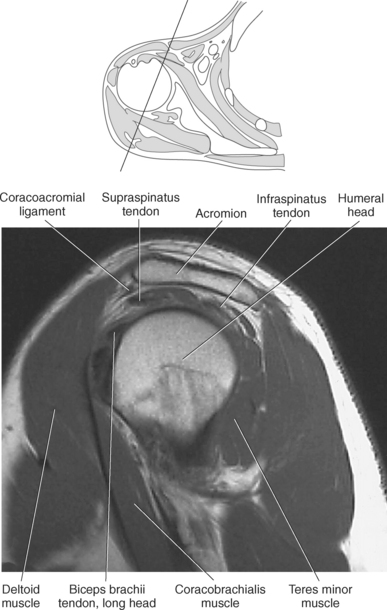

Figure 9.10 Sagittal oblique, T1-weighted MR scan of shoulder.

Key: cor, Coracoid process; cl, clavicle; sup, supraspinatus; ac, acromion; inf, infraspinatus; de, deltoid; tm, teres minor; gl, glenoid; sub, subscapularis; h, humerus; grt, greater tubercle; sc, scapula; glf, glenoid fossa; hh, humeral head.

The edge of the glenoid fossa is surrounded by a fibrocartilaginous ring termed the glenoid labrum (glenoid lip) (Figure 9.17). The glenoid labrum is a fold of the articular capsule, which functions to deepen the articular surface of the glenoid fossa. Superiorly, the labrum blends with the long head of the biceps brachii muscle. In cross section it appears triangular (Figure 9.18). The three glenohumeral ligaments (superior middle, and inferior) are thickenings of the fibrous capsule that surrounds the shoulder joint; they contributes to the formation of the glenoid labrum (Figures 9.17 and 9.19). They extend from the supraglenoid tubercle of the scapula to the lesser tubercle of the humerus. Also aiding in strengthening the fibrous capsule is the coracohumeral ligament that passes from the lateral side of the coracoid process of the scapula to the anatomic neck of the humerus (Figure 9.19). The coracoacromial ligament is another important ligament located on the anterior portion of the shoulder. As this ligament joins the coracoid process and acromion, it forms a strong bridge, termed the coracoacromial arch, which protects the humeral head and rotator cuff tendons from direct trauma and prevents displacement of the humeral head superiorly (Figures 9.17 and 9.19). The coracoclavicular ligaments help to maintain the position of the clavicle, in relation to the acromion, by spanning the distance between the clavicle and coracoid process of the scapula (Figure 9.19). The acromioclavicular ligament, at the acromioclavicular joint, provides support for the superior surface of the shoulder (Figures 9.17 and 9.19). The transverse humeral ligament is a broad band of connective tissue passing from the greater tubercle to the lesser tubercle of the humerus, forming a bridge over the intertubercular groove for protection of the long head of the biceps tendon (Figure 9.19). The ligaments of the shoulder are demonstrated in Figures 9.20 through 9.30.

Muscles of the scapula are described in Table 9.2 and demonstrated in Figures 9.34 through 9.52. The large deltoid muscle originates on the clavicle, acromion, and scapular spine to blanket the shoulder joint as it extends to insert on the deltoid tuberosity of the humerus. This powerful muscle forms the rounded contour of the shoulder and functions primarily to abduct the arm (Figure 9.48). The teres major muscle is a flat rectangular muscle that adducts and medially rotates the arm. It extends from the inferior angle of the scapula to the medial aspect or lip of the intertubercular groove of the humerus (Figure 9.49, A). The four remaining muscles, supraspinatus, infraspinatus, teres minor, and subscapularis, closely surround the scapula and compose the rotator cuff (Figures 9.49 through 9.52). The rotator cuff provides dynamic stability to the shoulder joint and allows for adduction, abduction, and rotation of the humerus. The supraspinatus, infraspinatus, and teres minor muscles are located on the posterior aspect of the scapula. The tendons of these muscles insert on the greater tubercle of the humerus. The supraspinatus muscle lies in the supraspinous fossa of the scapula and helps to abduct the arm. The tendon of the supraspinatus muscle is the most frequently injured tendon of the rotator cuff because of possible impingement as it extends under the acromioclavicular joint and continues over the humeral head (Figure 9.49, B). The infraspinatus muscle is a triangular muscle that lies below the scapular spine in the infraspinous fossa. It acts to laterally rotate the arm (Figure 9.49, A). Lying along the inferior border of the infraspinatus muscle is the elongated teres minor muscle, which also acts to laterally rotate the arm (Figure 9.49, B). The subscapularis muscle is the only muscle of the rotator cuff located on the anterior surface of the scapula; its tendon inserts on the lesser tubercle of the humerus (Figures 9.50 through 9.52). The subscapularis muscle acts to medially rotate the humerus. See sequential images through the shoulder (Figures 9.34 through 9.47).